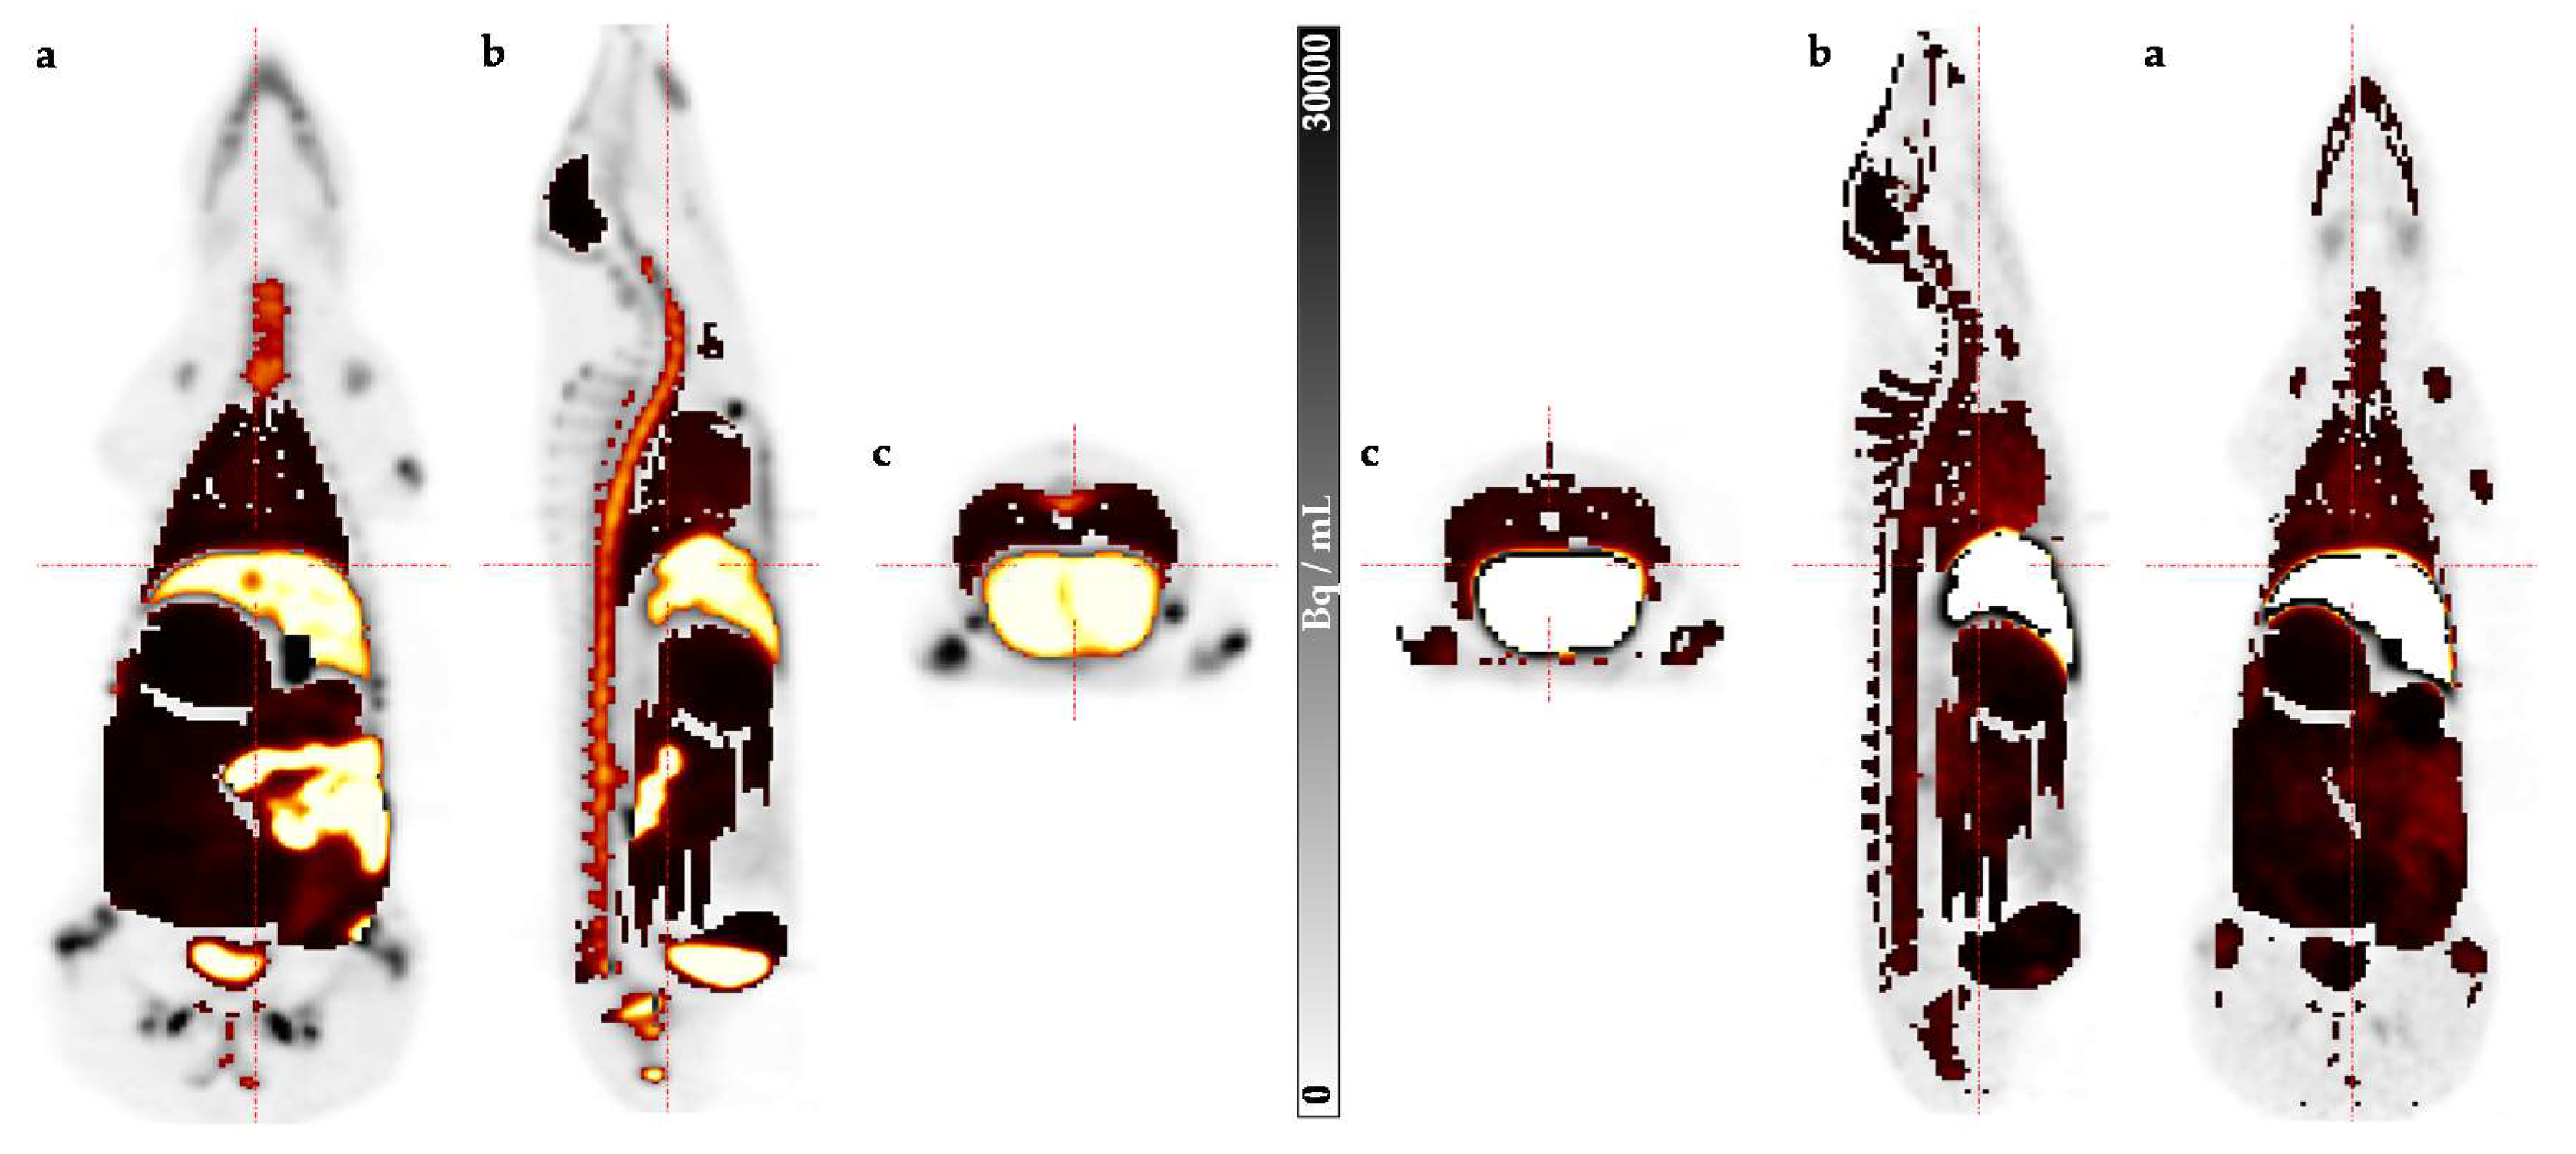

4.2. Preclinical Dosimetry Studies—In Vivo PET/CT Imaging in Pigs